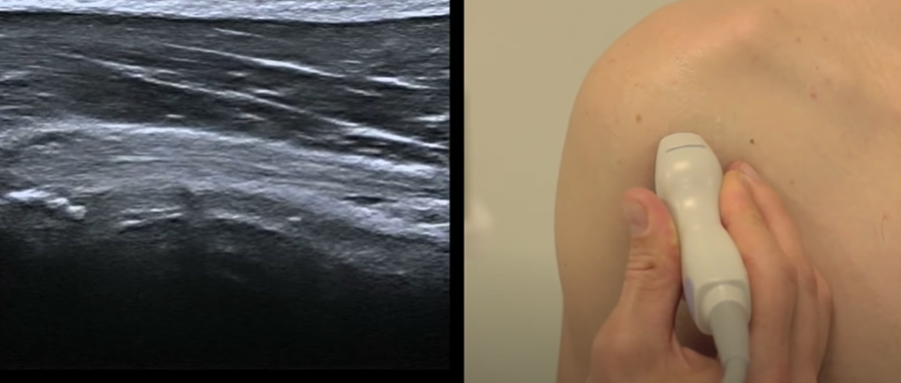

Infra-épineux

- Position neutre du début

- Coupe longitudinale

- Insertion sur le tubercule majeur (face oblique)

Coupe lnogitudinale

Petit rond

- Position neutre du début

- Sagittal sur le tubercule majeur

- Insertion du petit rond sur la face verticale

Coupe axiale